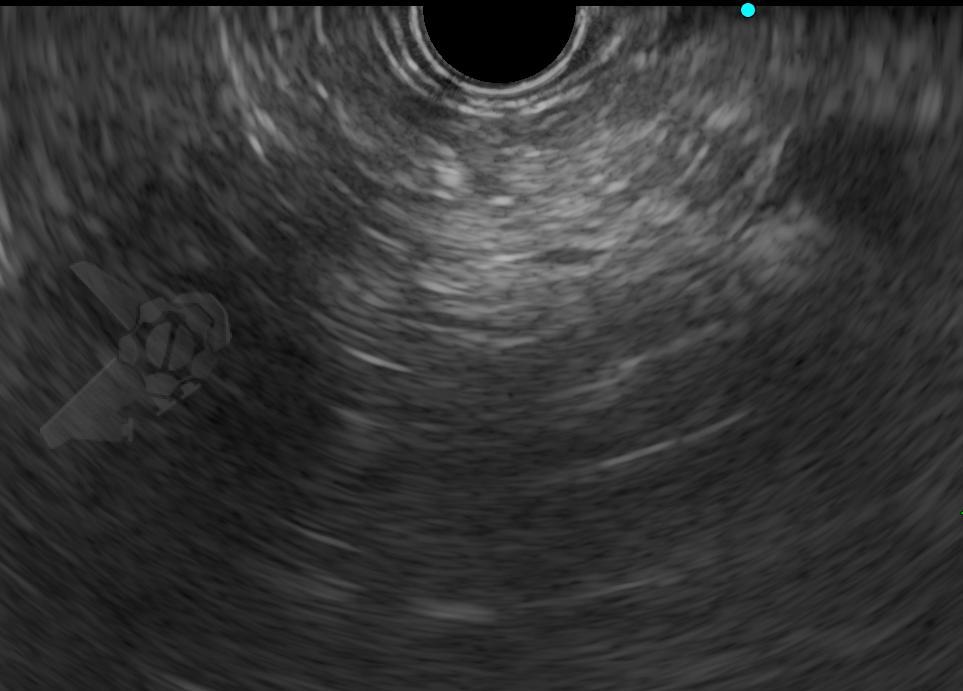

O diagnóstico no EUS se deu pela imagem pancreática hiperecoica difusa ou salteada, com borramento de seus limites e difícil caracterização do ducto pancreático principal ao invés do aspecto em “sal e pimenta” bem delimitado habitual – veja as imagens ilustrativas abaixo:

Imagens ilustrativas: